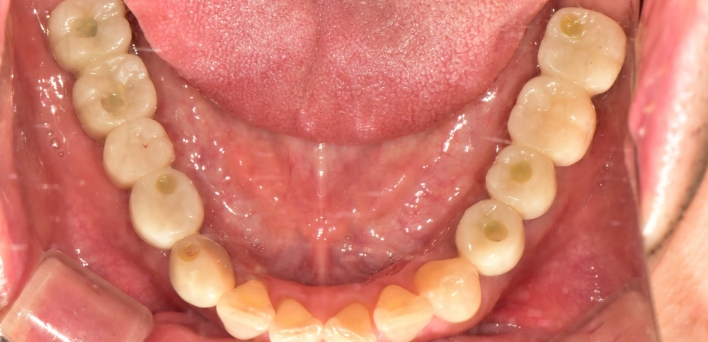

임플란트 : 손 ** 님 (50대)

치아가 있다는게, 아직도 정말 꿈만 같아요.

Before Before

2020.02.30

After After

※ 더서울치과의원은 의료법을 준수하며 위 케이스는 실제 환자의 동의를 얻은 사례로 치료 전, 후가 동일한 환경에서 촬영되었습니다.

환자 케이스에 따라 부작용이 발생할 수 있습니다. 이 부분은 의료진의 충분한 상담과 체크를 통해 예방하고 줄일 수 있습니다.

[임플란트 부작용] 수술 후 관리가 소홀할 경우 출혈, 주위염 등의 부작용이 발생할 수 있어 구강 위생을 철저히 유지하고, 정기적인 검진을 통해 상태를 점검하는 것이 중요합니다.

환자 특징

환자 특징01무치악 상태

환자 특징02수년간 무치악으로 지내심

임플란트가 불가능할것이라

생각하고 내원

위, 아래 6개씩 식립

디지털 풀아치 임플란트

임플란트 Before & After